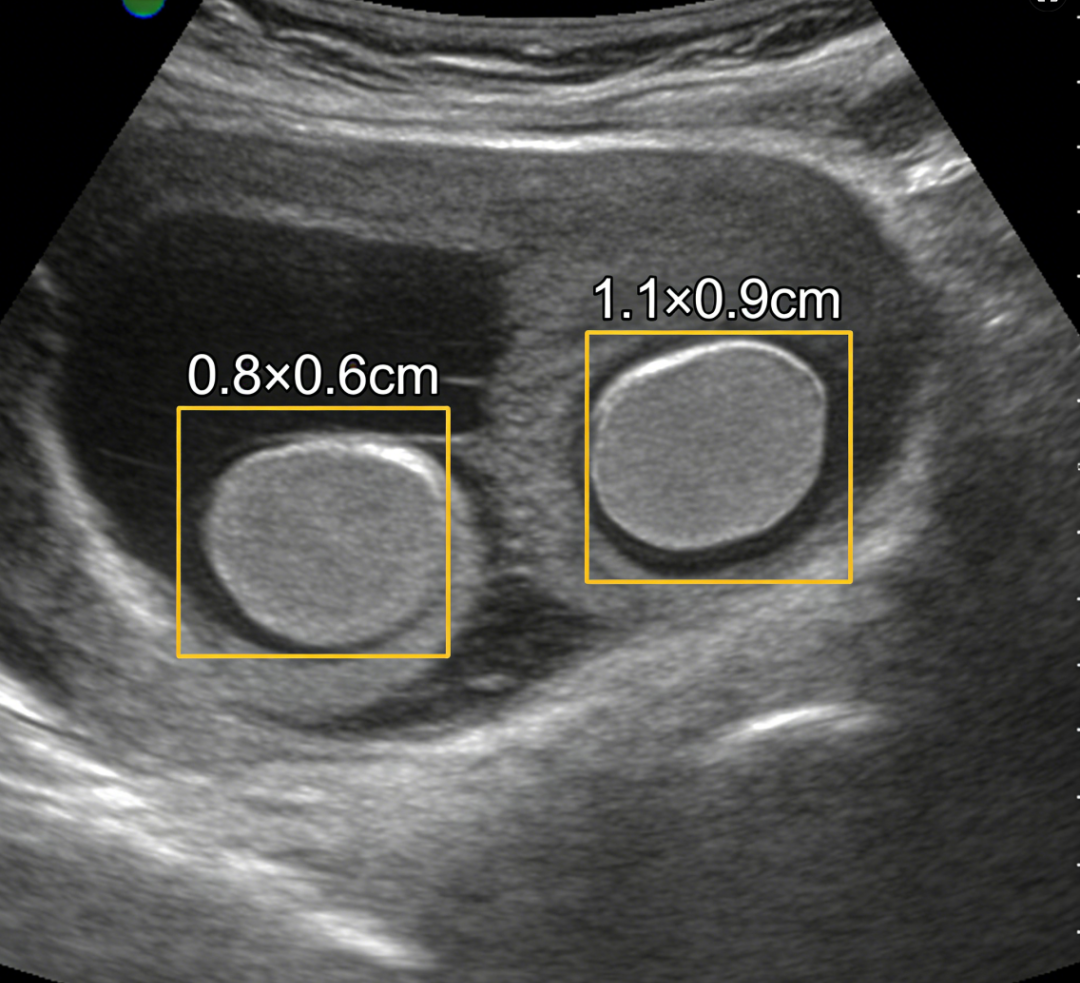

醫(yī)生判斷要不要手術(shù)

主要看結(jié)節(jié)的

?“顏值”(形態(tài))和 “脾氣”(性質(zhì))

不用切的 “乖寶寶”:

? ?形態(tài)規(guī)則? ?邊界清晰

? ?活動(dòng)度好? ?且考慮良性

比如:乳腺纖維瘤、增生結(jié)節(jié)。

這種結(jié)節(jié)就像臉上的小雀斑,看著有點(diǎn)煩,但基本不鬧事,定期復(fù)查就行。

建議切的 “壞家伙”:

? 形態(tài)不規(guī)則? ?邊界模糊

還伴有鈣化點(diǎn)

復(fù)查時(shí)發(fā)現(xiàn)它?“瘋長(zhǎng)”

甚至穿刺提示有惡性風(fēng)險(xiǎn)

這種結(jié)節(jié)就像一顆不定時(shí)炸彈,越早切掉越安心。